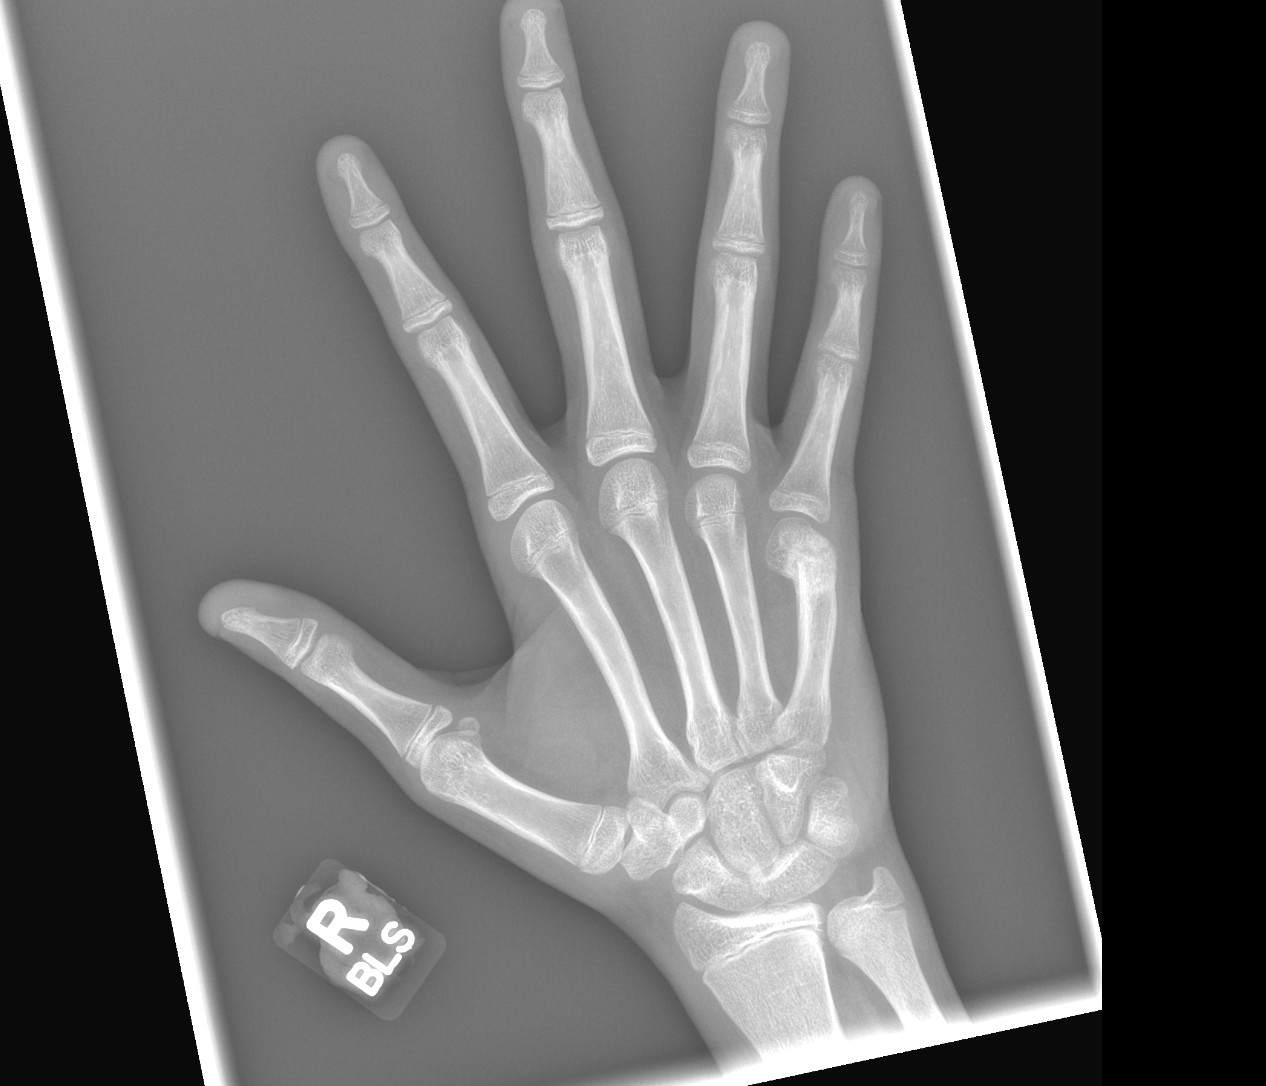

Info Images Findings Impression Reco/Acuity Case Images View Images / Launch Visage Case Notes History 2-month-old presents with decreased right arm movement, increased fussiness, and increased sleepiness for 2 days. Suspected non-accidental trauma. Exam Skeletal survey Prior Study none Dicom View Reference Material

Section 1 Submit Findings CB1550 Findings Skeletal Survey - Technique Check Skull AP/Lat Yes No Cervical and Thoracolumbar spine Yes No Chest X-Ray Yes No Ribs – Left/Right Oblique Yes No Abdominal X-Ray Yes No Pelvis with both hips Yes No Bilateral Humerus, Forearm, Hand Yes No Bilateral Femur, Tibia/fibula, feet Yes No Any additional lateral views of the extremities Yes No The exam is over or under penetrated. Yes No The exam may or may not be limited by overlying structures or soft tissues, body habitus, patient positioning, support devices, or motion. Yes No The area of concern is indicated by the patient, technologist, or care provider. Yes No The area of concern is included on the exam. Yes No Soft Tissues There is soft tissue swelling, indistinctness of fat/muscle planes, gas, or laceration in the area of clinical concern. Yes No There is an effusion, fat pad displacement, or fat fluid level. Yes No There is a radiodense or lucent foreign body. Yes No There are other densities, calcifications, post-surgical changes, or support devices in the soft tissues. Yes No Any support lines/tubes. Yes No Bone There is a break or interruption of the continuity of the cortical or cancellous bone. Yes No There is overriding of the trabeculae with apparent sclerosis. Yes No There is displacement of a fracture fragment. Yes No There is bowing of the bone in addition to the fracture at the apex of the bowed bone concerning for the greenstick. Yes No There is a spiral fracture of the leg concerning for toddler’s fracture. Yes No There is abnormal angulation or bulging of the cortical surface relative to the normal cortex which could be from a buckle or torus fracture. Yes No There is a displaced fragment which may be from avulsion by a tendon, ligament, or joint capsule or from a comminuted or other fracture. Yes No The stress trabeculae or other trabeculae of the cancellous bone are interrupted or otherwise abnormal. Yes No There is subperiosteal or endosteal reaction which could indicate a healing or subacute fracture or other abnormality. Yes No There is hard/soft callus formation. Yes No There is remodeling of the bone. Yes No There is a corner fracture or metaphyseal lesion that could be from nonaccidental trauma. Yes No There are multiple fractures of different ages. Yes No There are vertebral body/spinous process fractures. Yes No There are rib fractures. Location - posterior or lateral. Yes No There is scapular/sternal fracture. Yes No There are fractures of the digits. Yes No There are wormian bones. Yes No There are intrasutural bones. Yes No There is metaphyseal abnormality (lucencies, increased density, erosion) which may be from something other than injury such as stress, metabolic disease (e.g. rickets with loss or distortion of the zone of the provisional calcification), neoplasm (e.g. leukemia), heavy metals, inflammation, or infection. Yes No There are metaphyseal spurs. Yes No There are bony deformities involving multiple bones. Yes No The bones are gracile. Yes No There are non-healing fractures. Yes No There is/are focal or multifocal lytic/lucent, blastic/sclerotic or mixed density lesion(s) or other abnormality. Yes No Overall bone density is increased or decreased with or without thinning or thickening of the cortical or cancellous bone. Yes No Growth plates, ossification centers, apophyses The growth plate(s) is/are abnormal. Yes No There is widening of the physis from a fracture with or without displacement of the epiphysis (Salter-Harris I). Yes No There is a fracture through the physis which then extends into the metaphysis with or without angulation or displacement (S-H II). Yes No There is a fracture through the physis which then extends into the epiphysis and is intra-articular, with or without angulation or displacement (S-H III). Yes No There is a fracture through the metaphysis, physis, and epiphysis which extends into the joint space with or without angulation or displacement (S-H IV). Yes No There is narrowing of the physis from a compression fracture (S-H V). Yes No The apophysis, epicondyle, secondary ossification center, or accessory ossicle is displaced or otherwise abnormal. Yes No The ossification centers are underdeveloped. Yes No Joints and alignment There is an effusion, fat pad displacement, or fat fluid level. Yes No The epiphysis or subchondral bone is fractured, interrupted, flattened, compressed, impacted, displaced, or otherwise abnormal. Yes No There is an intra-articular loose body or chondrocalcinosis. Yes No The joint is widened, narrowed, dislocated, malaligned, or incongruent. Yes No There is pseudoarthrosis. Yes No Other findings There are developmental changes or other anatomic variants or other existing conditions that may or may not be contributing to symptoms which can or should be further evaluated non-emergently or are otherwise incidental. Yes No The remainder of the exam is abnormal for age. Yes No The lungs show focal airspace opacity. Yes No There is pneumothorax. Yes No There is organomegaly. Yes No There is intra-abdominal calcification. Yes No There is displacement of the bowel loops. Yes No There is free intraperitoneal air. Yes No The bowel loops are dilated/obstructed. Yes No There is paraspinal soft tissue abnormality. Yes No